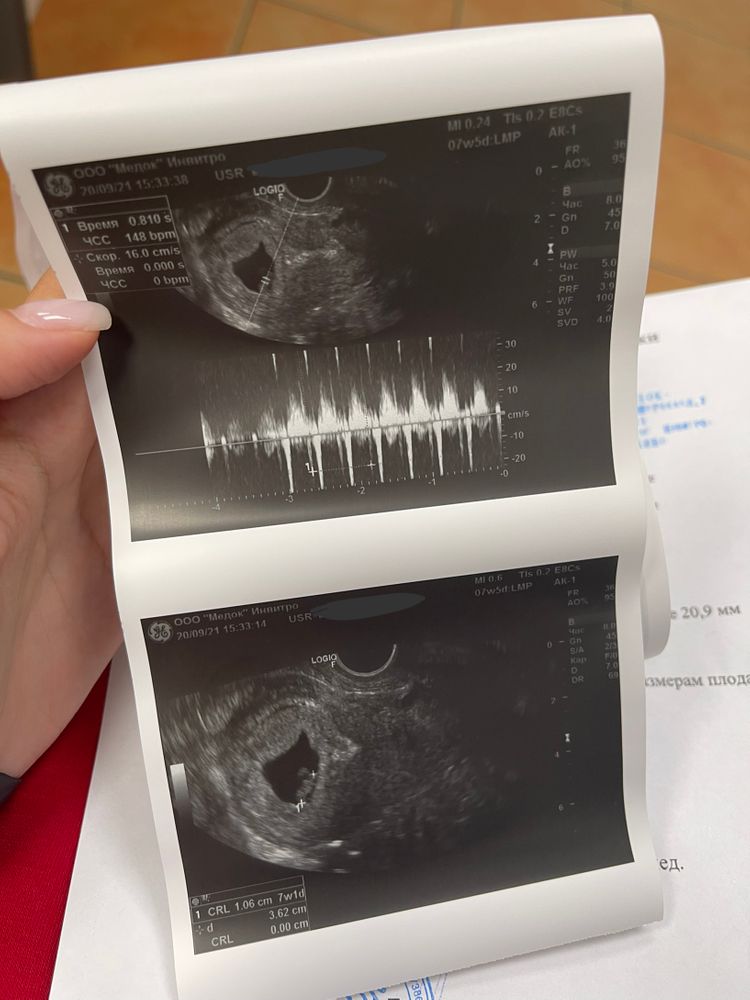

Ну и сегодня состоялась наша первая встреча 😍 сколько страха у меня было перед походом на узи , вы бы знали ) но как только доктор ввёл датчик , сразу сказал «ну вот и ваше чадо» и включил сердечко 🥰 думала обсикаюсь от счастья 😄

Тонус - последствие перелёта , узист сказал , чтобы я особо на этот счёт не переживала ) ну я и не переживаю 😄